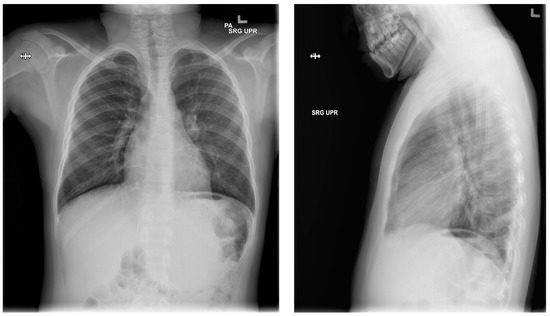

Figure 6.

Post-operative chest X-rays, showing reversed pleuroperitoneal shunt in right chest and abdomen.